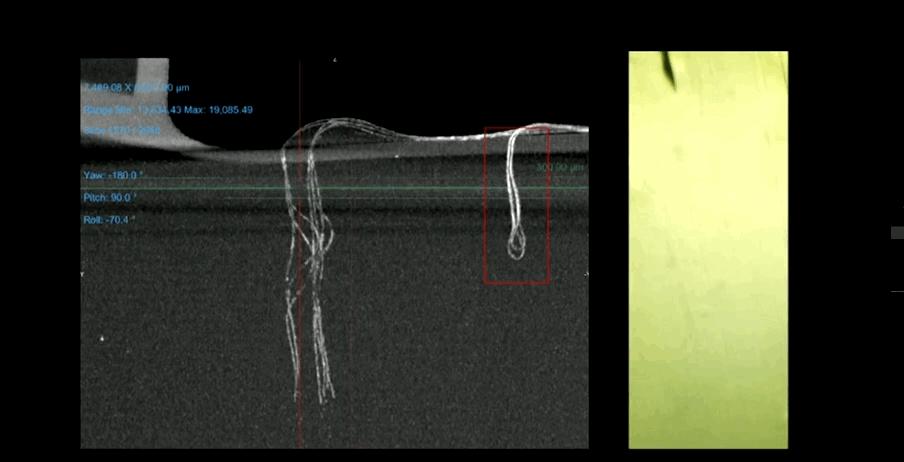

在电极方面,Neuralink在2022年的进展并没有很显著,仍然采用的是19年发布会中的Thread,主要的进展是在配合电极植入大脑的引针上(有点像缝纫机的引针),由于引针的大小会直接关乎对硬脑膜以及脑内血管组织的侵入受损程度,所以在过去的一段时间内,Neuralink主要对引针以及电极的制作工艺进行了优化,提高了产出效率以及测试验证周期

但是,优化后的引针和电极在植入大脑后仍然存在一定的耦合问题,即引针会讲电极往后拉扯一定距离,为了解决这个问题,Neuralink专门研制了大脑模具进行测试。

报告中展示了植入机器可以把几微米级别的像丝线一样的电极植入大脑,15分钟即可植入64根脑电极,可以精准避开大脑血管位置